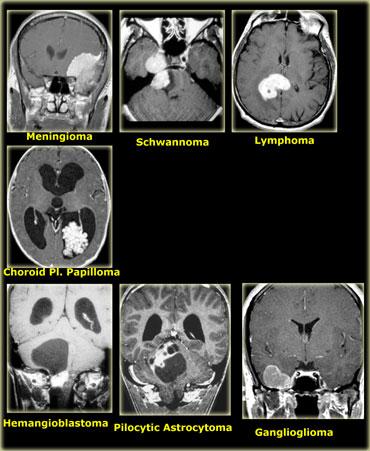

Ngấm thuốc đồng nhất có thể thấy trong:

- Di căn não

- U lympho

- U tế bào mầm (Germinoma) và các khối u tuyến tùng khác

- U tuyến yên đại thể (Pituitary macroadenoma)

- U sao bào dạng lông (Pilocytic astrocytoma) và u nguyên bào mạch máu (Hemangioblastoma) (chỉ thành phần đặc)

- U hạch thần kinh đệm (Ganglioglioma)

- U màng não (Meningioma) và u bao thần kinh (Schwannoma)

Các khối u độ thấp có ngấm thuốc: u hạch thần kinh đệm – ganglioglioma (trái) và u sao bào dạng lông – pilocytic astrocytoma (phải)

U hạch thần kinh đệm (ganglioglioma) và u sao bào dạng lông (pilocytic astrocytoma) là các ngoại lệ của quy tắc này: chúng là các khối u độ thấp nhưng ngấm thuốc rõ rệt.